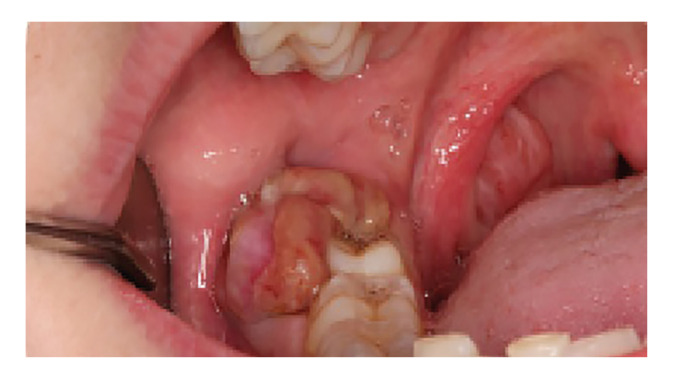

Abstract Image